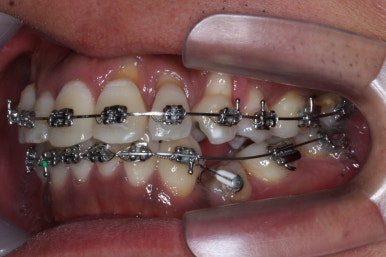

치료 1년 5개월째의 모습입니다.

작은 어금니가 어느 정도 올라왔다고 판단되어, 본격적으로 틈을 줄이기 시작했어요.

오른쪽 아래 맨 뒤어금니는 예후가 불량하여 살려쓰기 힘들다고 판단이 되어 발치했어요. 추후에 임플란트를 하셔야 합니다.

부산치아교정 키다리아저씨치과에서 치료를 시작한지 2년 경과시 모습입니다.

이 뽑은 틈도 어느 정도 다 닫혀가고, 애를 먹이던 왼쪽 아래 작은 어금니도 많이 좋아졌어요.

여전히 약간은 불만족스러워 갖가지 방법을 동원해서 바로 잡아주고 있어요.

2년 2개월째 이빈다.

이제 거의 다 되어간다고 보면 되겠고, 좀 더 디테일한 마무리를 하고 끝내면 되겠습니다.